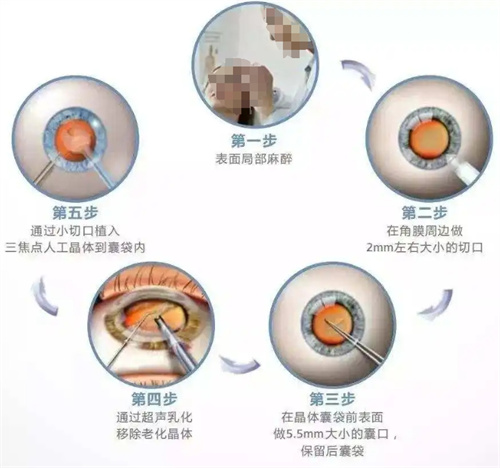

人工晶体置换需通过角膜切口将人工晶体植入眼内,若术中无菌操作不严或术后护理不当,细菌可能通过切口侵入眼内,引发眼内炎。

人工晶体依赖周边囊袋固定,若术中囊袋撕裂、术后剧烈运动或眼部受到外力撞击,晶体可能发生偏移或脱位。